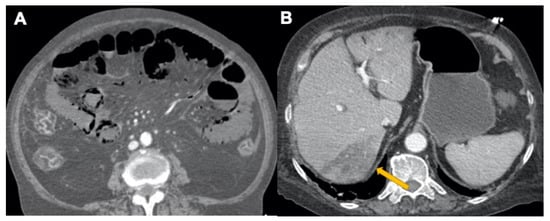

3.3. Abdominal Manifestations